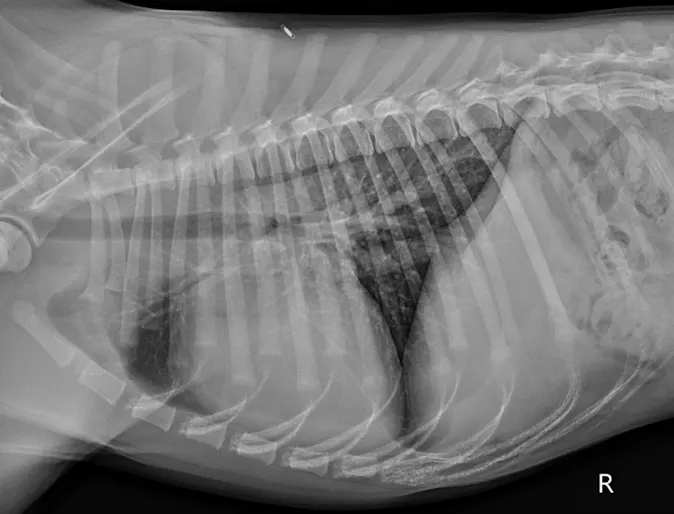

Cardiac Changes and Congestive Heart Failure Secondary to Chagas Disease

Diagnostic Imaging

The patient presented to GCVS Internal Medicine Service for evaluation of ascites.